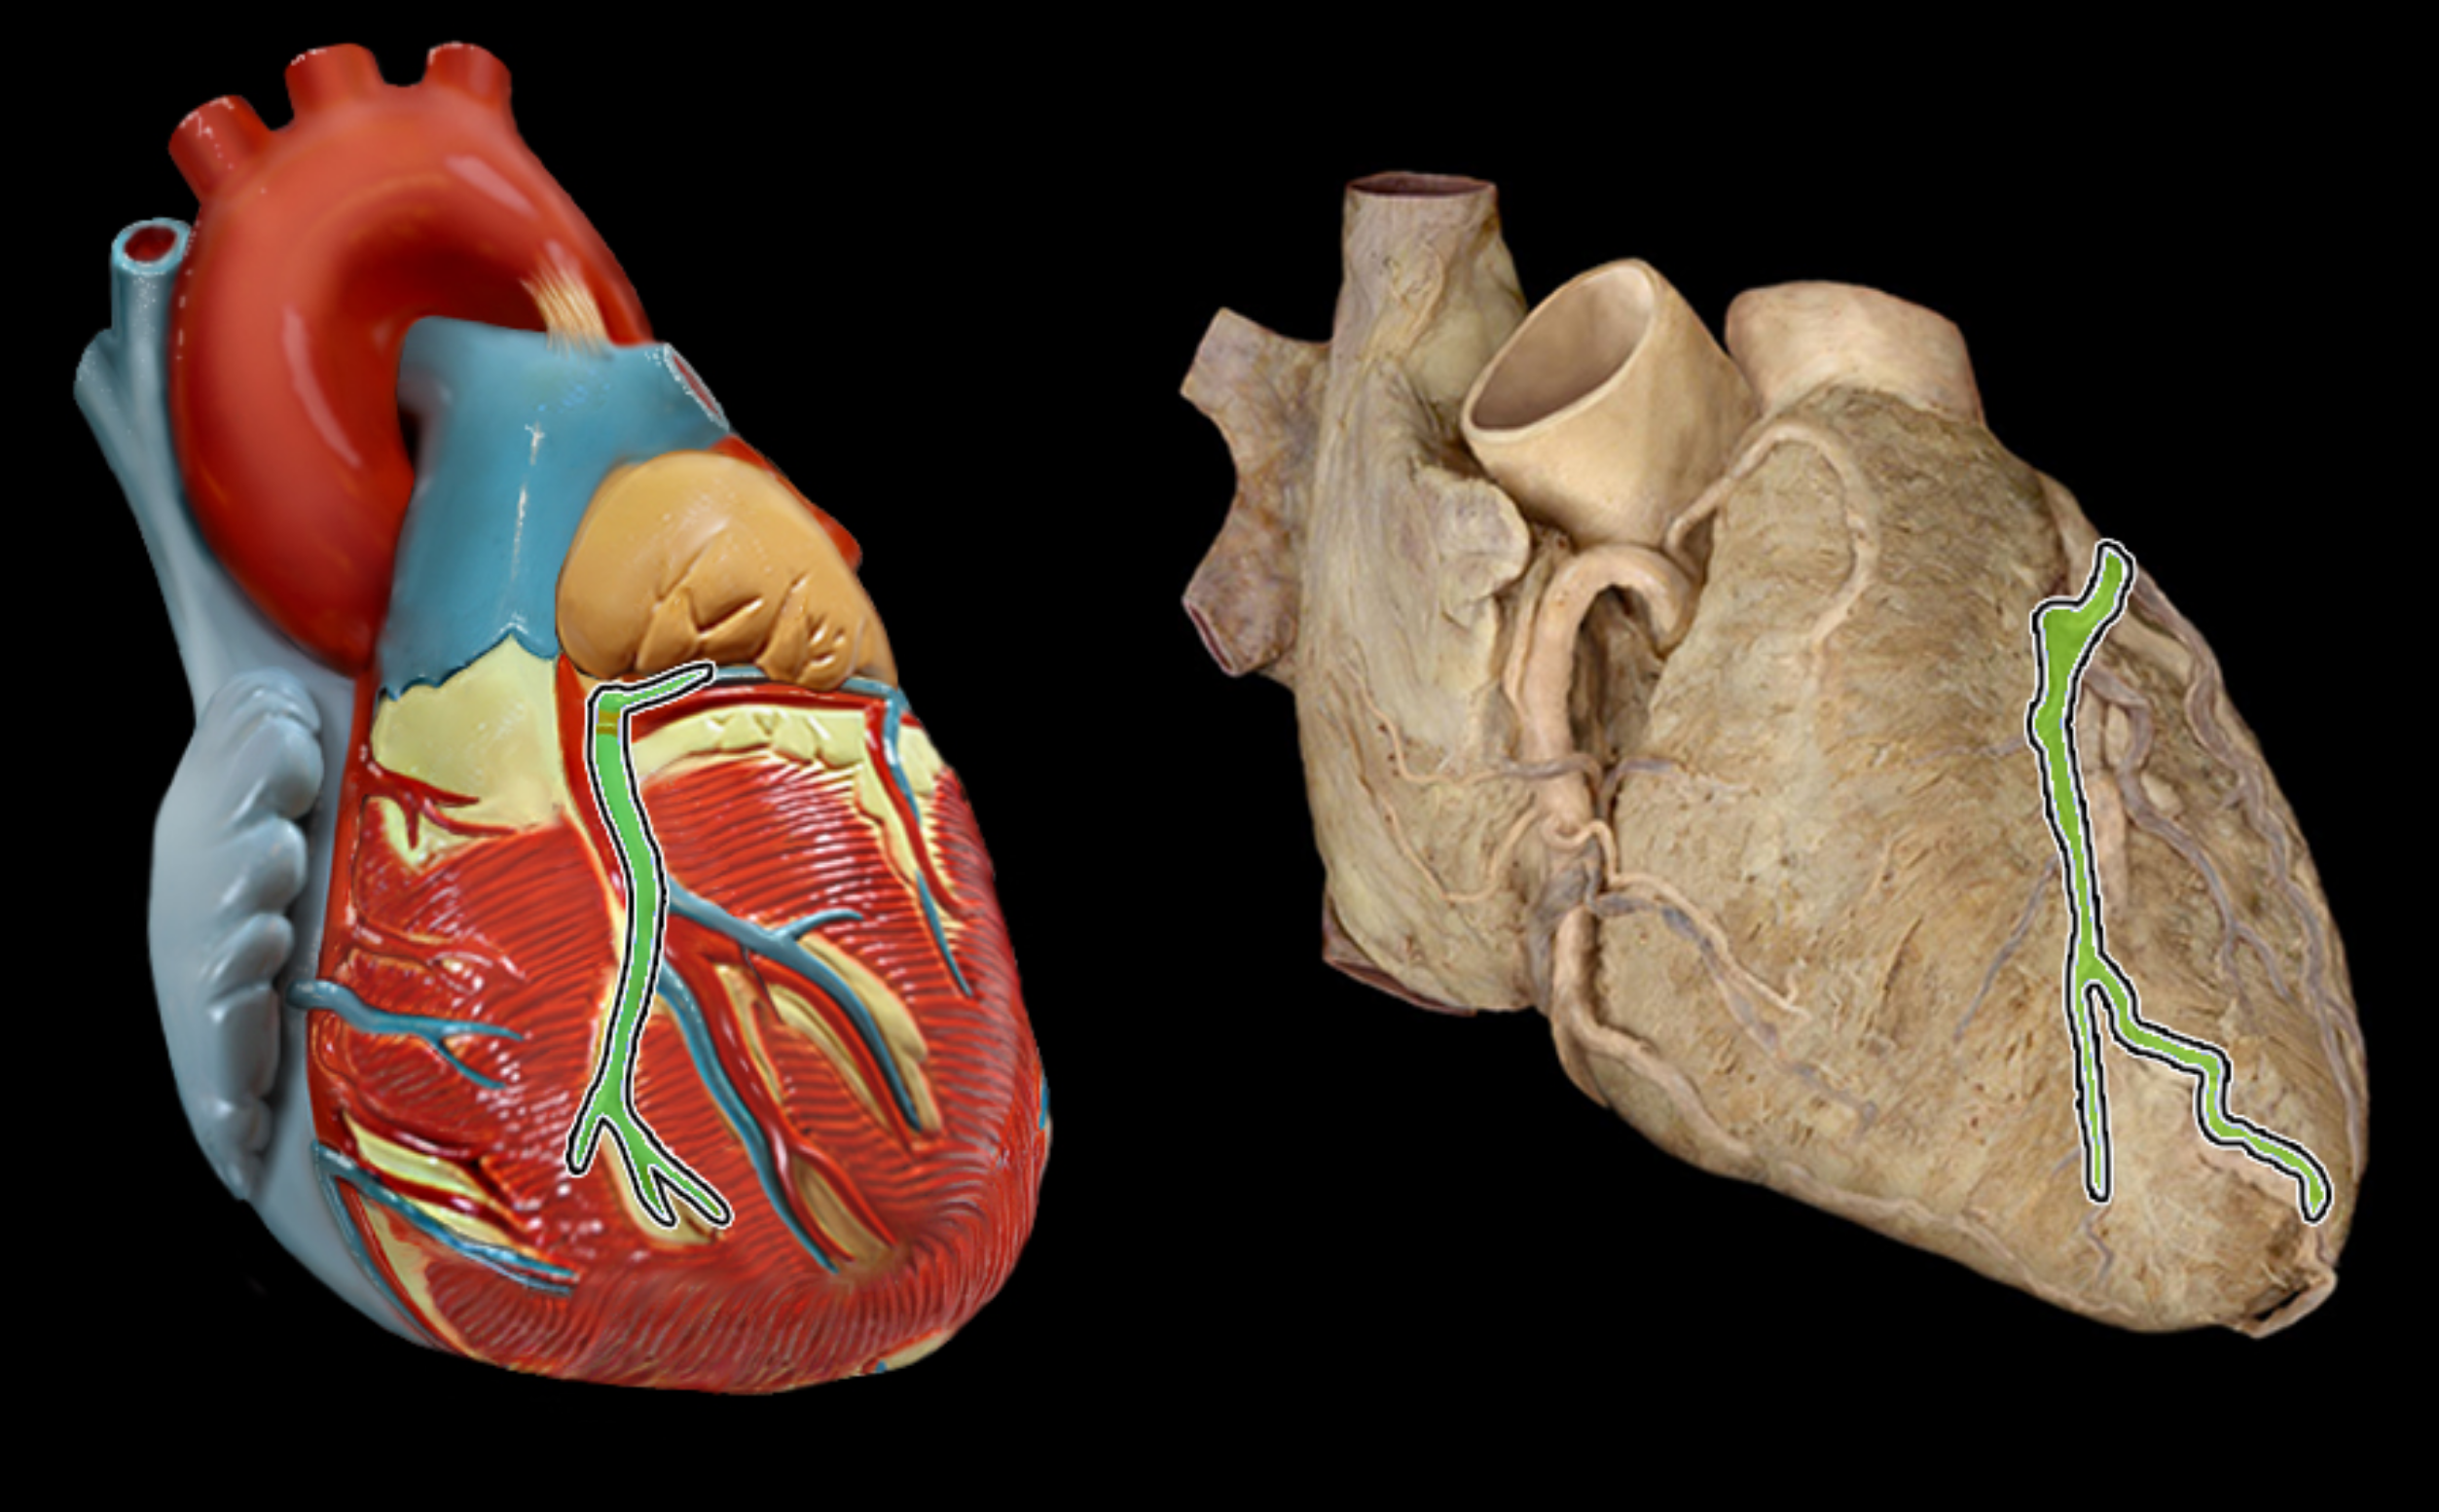

Coronary sinus

Great cardiac vein